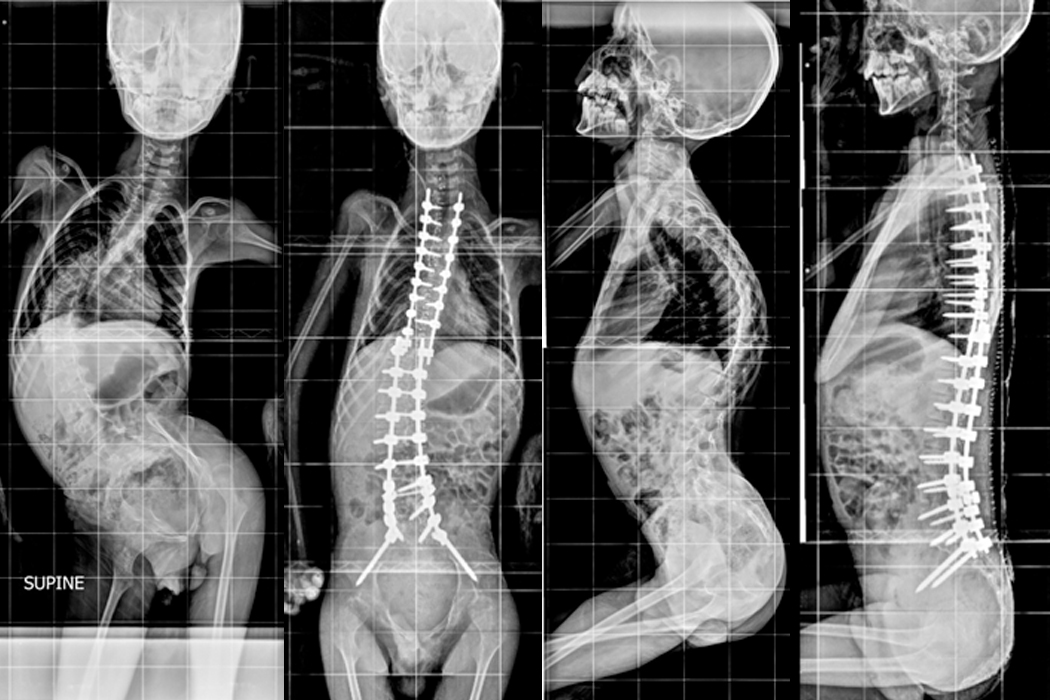

11 year old kid presented with deformity of back with poor sitting balance and breathing problems. He was diagnosed with Spinal Muscular Atrophy with severe kyphoscoliosis when he was 4 years old. He was initially given Halo gravity traction to aid the surgery and improve his breathing function. Posterior Scoliosis correction done in stages on 25.08.2020 and 01.09.2020.

Hover over the image to view Pre & Post-op X-Rays